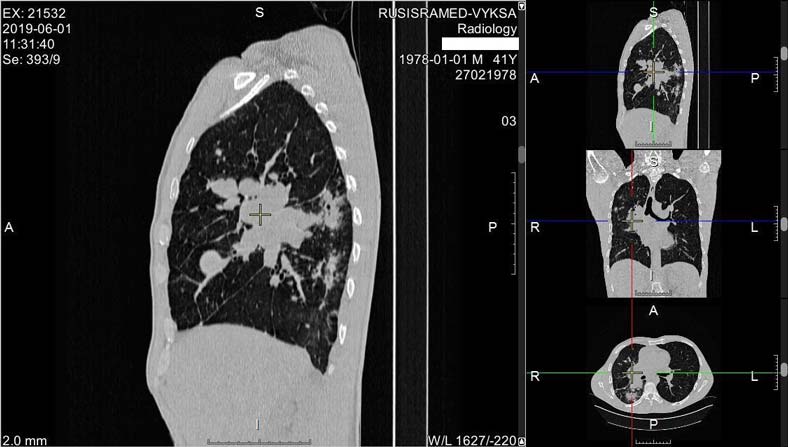

01.06.2019 пациенту проведена мультиспиральная компьютерная томография органов грудной клетки. Заключение: компьютерно-томографические признаки инфильтративного туберкулёза правого лёгкого в фазе распада (рис. 1). Лимфаденопатия средостения (рис. 2), генез под вопросом, туберкулёз бронха под вопросом, сочетание с раком лёгкого под вопросом.

Рис. 2. Мультиспиральная компьютерная томограмма органов грудной клетки. Снимки пациента от 01.06.2019: лимфаденопатия средостения